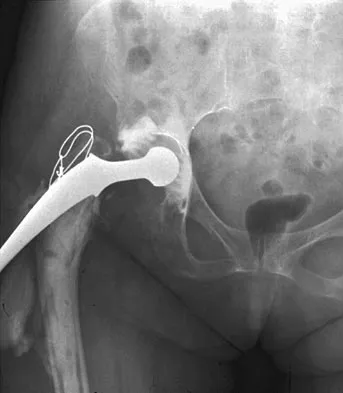

A 42-year-old man sustained the periprosthetic fracture shown in Figures 19a and 19b. The femoral component is well fixed. What is the next most appropriate step in management?

Explanation

The patient has a periprosthetic fracture below the femoral stem. The component is porous coated and well fixed. Open reduction and internal fixation, leaving the stem in place, can be performed when bone quality is good. Plating with or without allograft struts and supplemental cerclage fixation generally is acceptable. If the component is loose, revision to a longer device is recommended with appropriate stabilization of the fracture using the aforementioned methods. If bone loss has occurred, allograft supplementation or a tumor prosthesis may be indicated. Fractures located well below the stem tip can be treated without regard for the prosthesis. Closed reduction and bracing is not associated with good results for periprosthetic femoral fractures. Retrograde intramedullary nailing is not appropriate for this fracture. Duncan CP, Masri BA: Fractures of the femur after hip replacement. Instr Course Lect 1995;44:293-304.